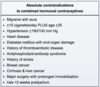

What is the most common side effect of combined oral contraceptives?

Breakthrough bleeding

other side effects include hypertension, increased risk of venous thromboembolism, and increased risk of cervical cancer